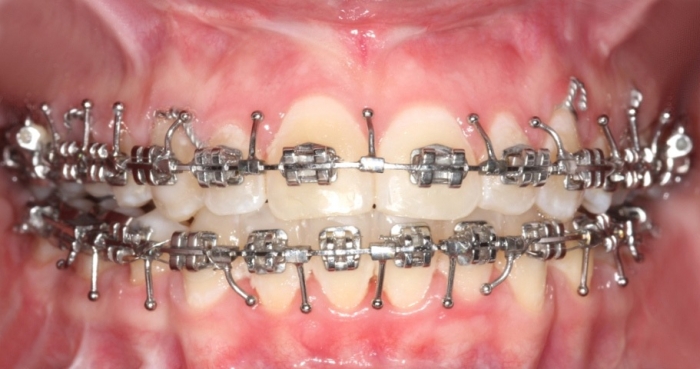

Mordida inicial